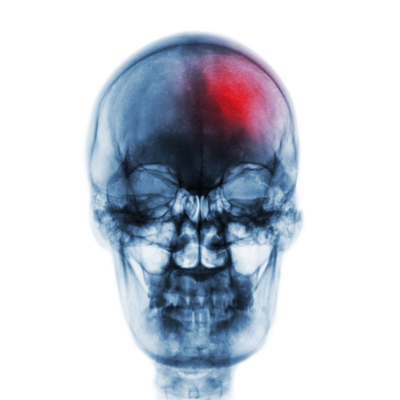

(Left) MRI before intervention. Pathological flow signal in the area of the left occipital condyle can be seen. (Right) MRI after intervention. No more pathological flow signal, and the tinnitus is visible.Images courtesy of UKE Hamburg-Eppendorf and Dr. Fabian Flottmann.